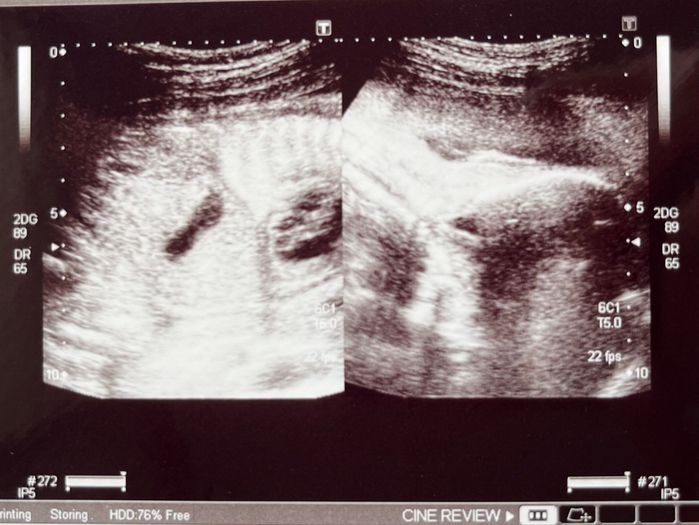

引っ越しのため、都内の病院から新居近くのクリニックに転院し、妊婦健診を受けたときのこと。いつもより超音波エコー検査に長い時間がかかっているな~と感じ、医師が怖い顔をしていることに気づきました。もしかして何かあるのか・・・と不安に思っていたら『赤ちゃんの心臓の形に異常が見られる。詳しい検査が必要です』と言われました。

「検査の結果を夫と2人で聞きに行くと、医師からは『左心低形成(さしんていけいせい)』という先天性の心臓病の可能性が高いと言われました。そのほかにも聞いたこともない病名がたくさん並び、脳や胆道閉鎖などほかの病気の可能性もあるとのこと。医師から説明される内容があまりに重く、息をするのも忘れて苦しくなってしまうほど。面談の部屋を出るときにはめまいのようにくらくらして気持ち悪くなる、そんな状態でした。